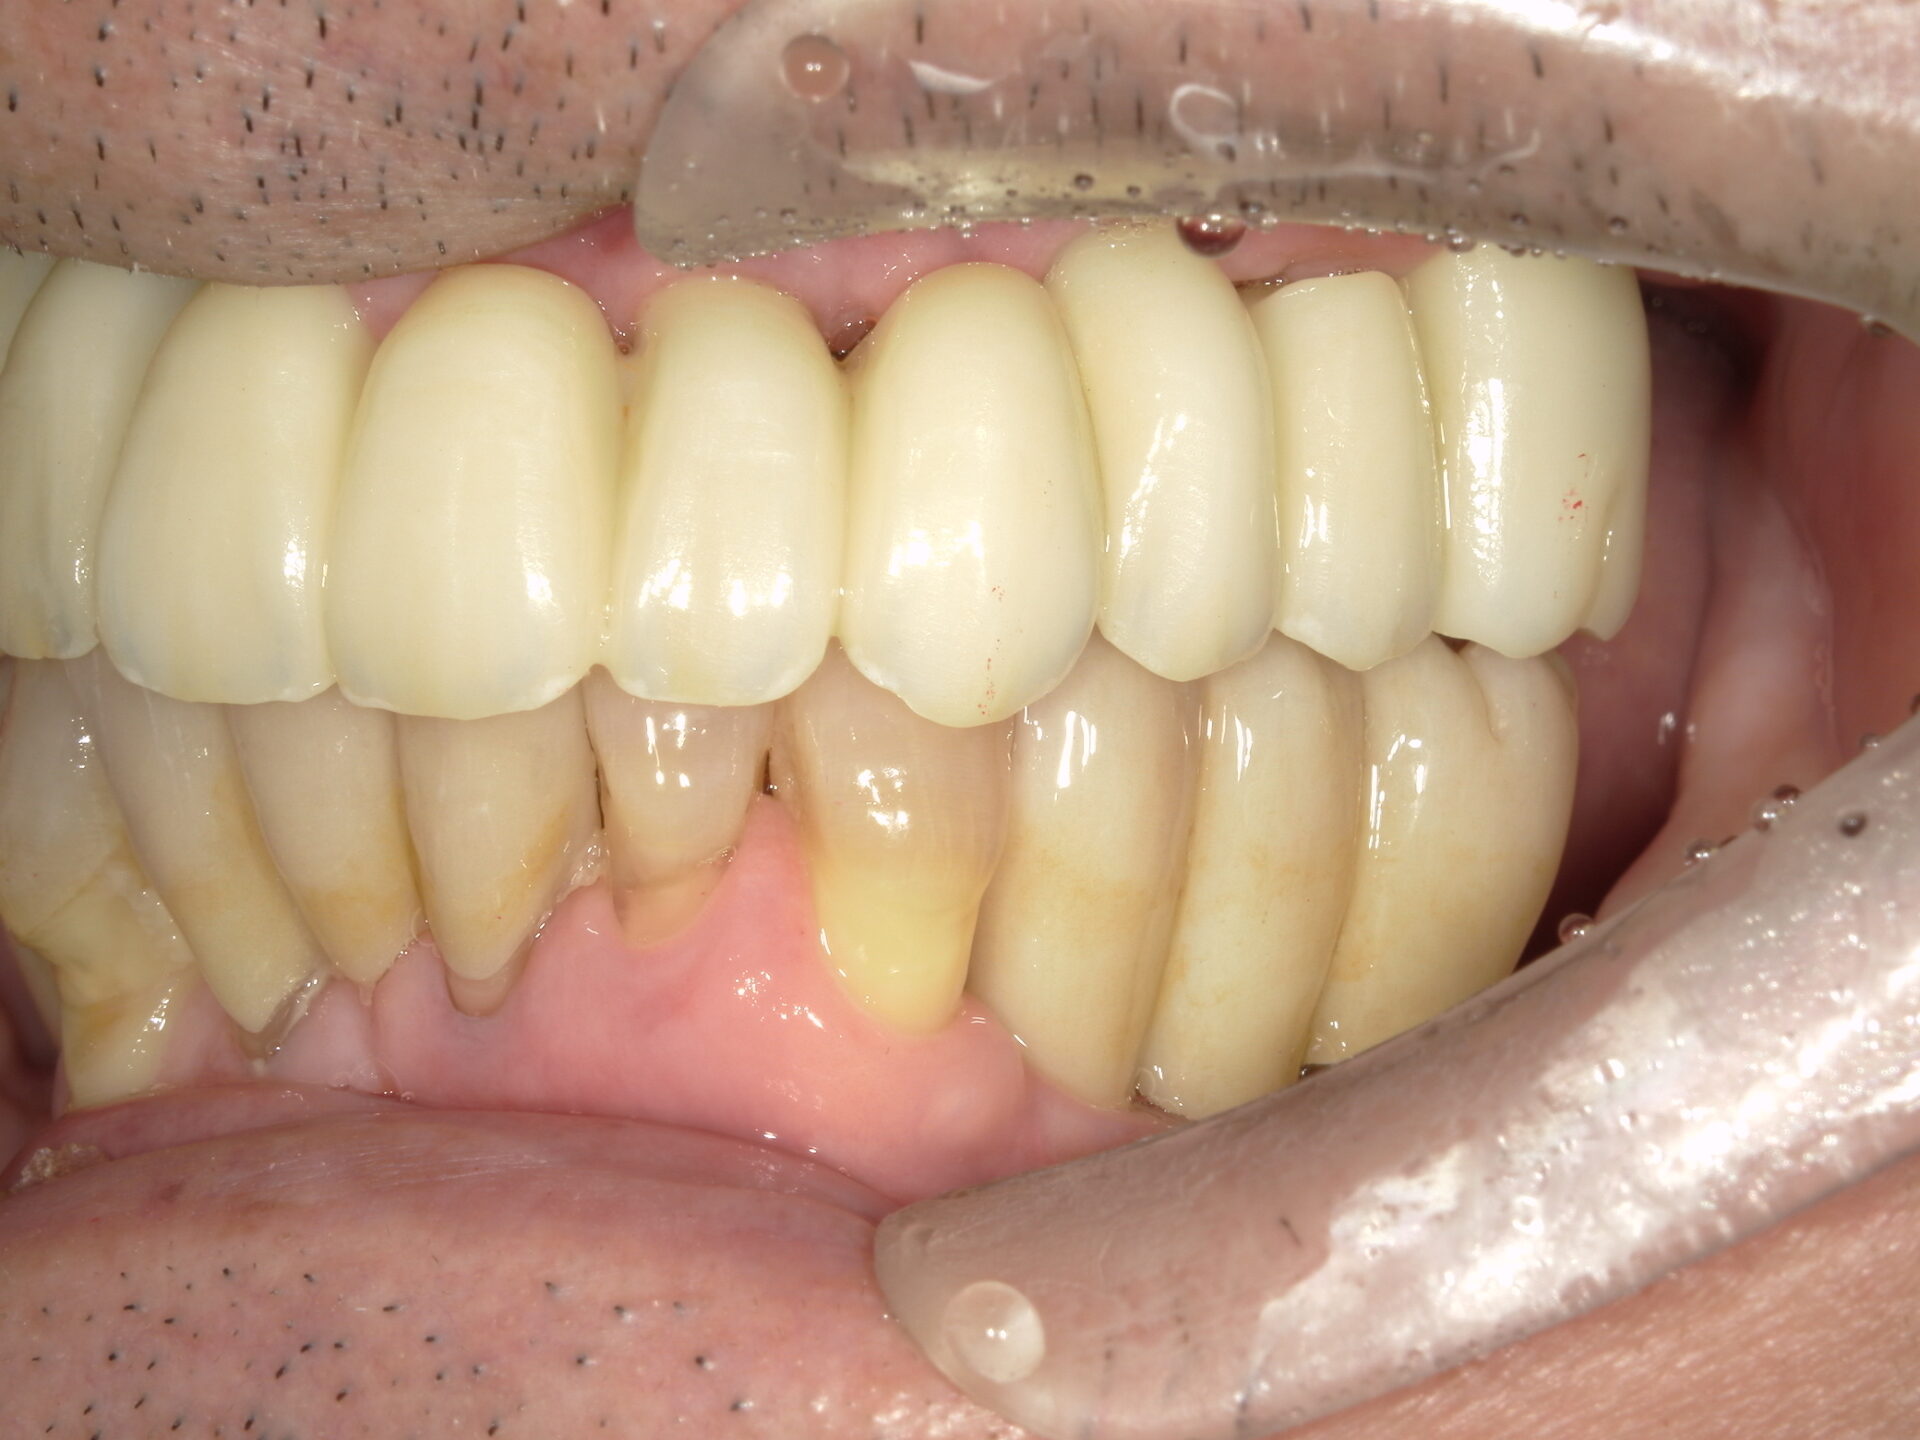

before

after

患者さんの年齢 50代 男性 症状 何も噛めない 治療内容 インプラント治療(オールオン4) 費用 費用900万(税抜) 治療期間・回数 治療期間2年・通院回数12回 メリット なんでも噛めるようになる 見た目が綺麗 デメリット・リスク 骨造成などで費用が増える場合がある - インプラント治療